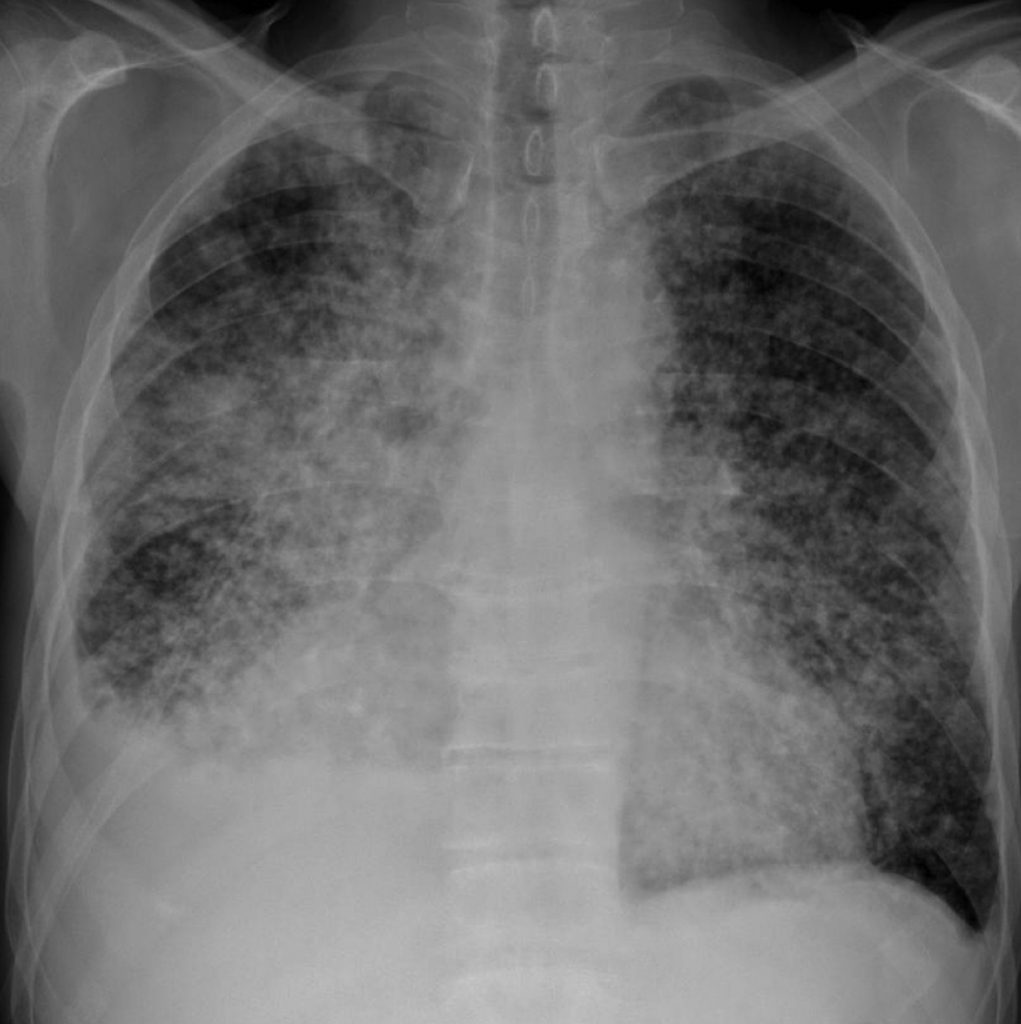

Fig. 101.6. Radiographie thoracique.

Syndrome micronodulaire bilatéral diffus associé à un épanchement pleural droit. Miliaire carcinomateuse sur néoplasie bronchique du lobe inférieur droit.

Source : CERF, CNEBMN, 2022.